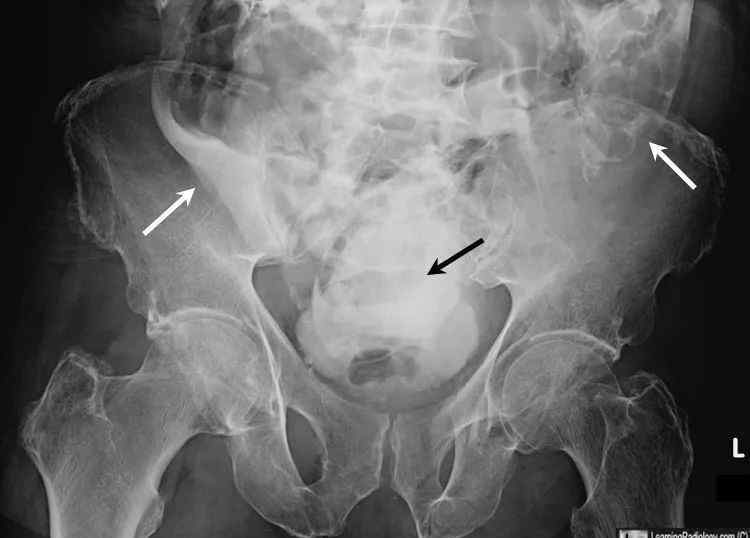

患者56岁。与机动车相撞后的膀胱造影如图1所示。你考虑什么诊断?

图1对比剂注入膀胱后的骨盆平片

参考答案:腹膜内膀胱破裂

第二型:腹腔内膀胱破裂,通常继发于穿透伤或医源性损伤,多为膀胱充盈时腹部外伤所致。膀胱圆顶是最薄弱的部位,所以最容易破裂。造影剂可以通过成像检查在结肠旁沟和小肠环之间观察到。

腹部平片:1。“梨形”膀胱;2.麻痹性肠梗阻;3.回肠循环上移;4.造影剂呈火焰状,渗入膀胱周围脂肪,可延伸至结肠旁沟甚至大腿/前腹壁。因为腹膜内膀胱破裂有可能发展为化学性腹膜炎,其破裂死亡率最高,需要紧急手术修复。

图2腹膜内膀胱破裂。注射到膀胱中的造影剂延伸到膀胱圆顶的外部,并勾勒出下腹部肠袢